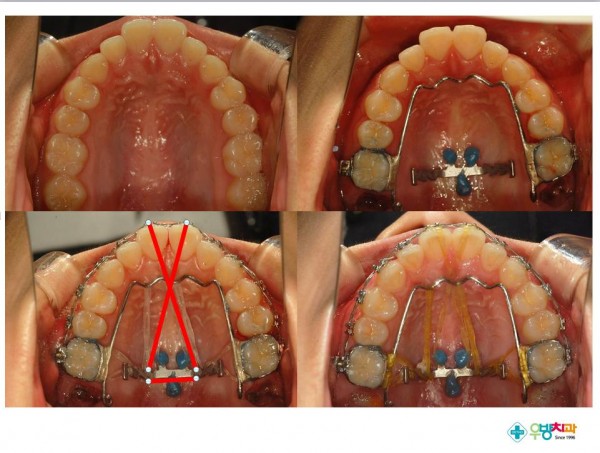

[Gummy smile, protrusion 환자 적용]

Nonextraction treatment with temporary skeletal anchorage devices to correct a Class II Division 2 malocclusion with excessive2.pdf